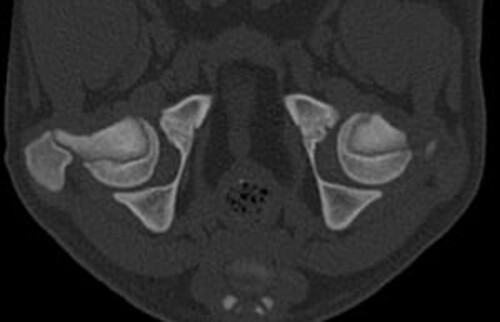

Bilder einer vollständigen Hüftdysplasie-Untersuchung beim Hund

In unserer Tierklinik bei Karlsruhe können unsere Ärzt*innen durch die Aufnahmen eine zuverlässige Prognose für die Weiterentwicklung der Hunde-Hüfte stellen.

Schwarz-weißes CT-Querschnittbild der Hüftgelenke eines Tieres.